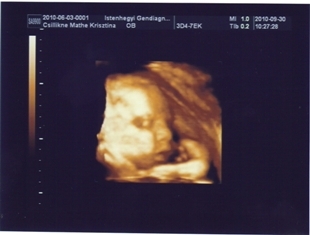

Annus! Megy a drukk 4D-re Képeket hozzál ám!!